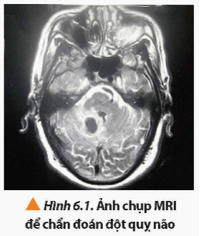

Mở đầu trang 39 Chuyên đề Vật Lí 12: Để chẩn đoán những bất thường của não (Hình 6.1) và tuỷ sống; các bệnh liên quan đến tim mạch; bệnh liên quan đến các cơ quan nội tạng như gan, lá lách, phổi, … bác sĩ thường tư vấn và yêu cầu bệnh nhân chụp ảnh cộng hưởng từ (MRI – Magnetic Resonance Imaging) để thu được những hình ảnh chi tiết hơn các kĩ thuật chụp ảnh khác như siêu âm, chụp ảnh cắt lớp (CT). Từ đó góp phần đáng kể giúp quá trình chẩn đoán của bác sĩ được chính xác hơn. Vậy kĩ thuật chụp cộng hưởng từ là gì và hoạt động dựa trên những cơ sở vật lí nào?

Để chẩn đoán những bất thường của não (Hình 6.1) và tuỷ sống; các bệnh liên quan đến tim mạch